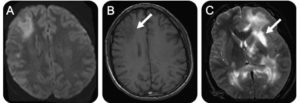

УЗ — диагностика с допплерографией выявляет нарушения в сосудах головного мозга (асимметрия, повышение венозного тока крови, стеноз, атеросклероз). КТ (компьютерная томография), определяет перенесенные инфаркты, скопление жидкости в полостях и истончение тканей (атрофия мозговых структур).

Наиболее достоверные и точные результаты возможны, получить только при исследовании с помощью магнитно — резонансной томографии (МРТ) черепа. Изображение получают путем взаимодействия электромагнитного поля с атомами водорода.

Данная диагностика позволяет оценить функционирование нейронов и обнаружить изменение плотности тканей мозга. Выявив бессимптомные стадии очагового поражения, возможно, начать своевременную терапию.

МРТ позволяет получить снимки в трех плоскостях (поперечная, продольная и фронтальная) и выявить причину нарушения питания мозговых структур:

Выявленная патология при помощи МРТ, позволяет оценить скорость прогрессирования заболевания и выбрать правильную тактику лечения.

Магнитная резонансная томография является одним из самых используемых методов в выявлении нарушений циркуляции крови головного мозга. Благодаря трехмерному изображению специалист может проанализировать все протекающие процессы и увидеть нарушения или новообразования.

Метод МРТ используется в первую очередь для диагностики. Применяются так же неврологические исследования и УЗИ тканей мозга.

Чтобы выявить патологические изменения, происходящие в ГМ, проводят магнитно-резонансную томографию.

Это единственный метод узнать, что именно происходит под черепной коробкой, увидеть все неблагоприятные процессы в структуре мозга, оценить возможные последствия и сделать максимально точный прогноз развития недуга.

В диагностике очаговых поражений головного мозга МРТ – «золотой» метод, способный дать наиболее точную оценку болезни. Он является не инвазивным, быстрым и высокоинформативным.

МРТ позволяет определить наличие очага поражения, а также провести сравнительный анализ полученных снимков со снимками здорового мозга. На них практически все очаги выглядят как светлые пятна различных размеров.

Помимо этого, магнитно-резонансная томография помогает точно установить количество очагов. Единичные изменения в головном мозге наблюдаются у всех пациентов в возрасте старше 50 лет. В подобных случаях необходимо следить за динамикой развития очага, а также принимать меры по ликвидации причин поражения ГМ.